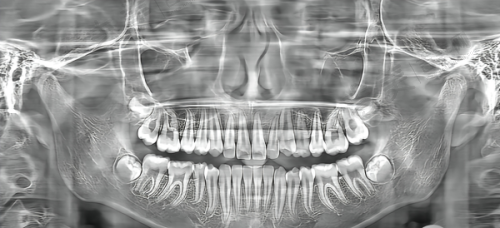

作为二级口腔专科医院,苏州华夏口腔医院的科室设置和设备远超普通诊所。它的牙体牙髓病科、牙周病科、口腔修复科、正畸科、种植中 心为苏州市临床重点专科,还细分了11个临床科室,涵盖儿童牙科、颌面外科、颞下颌关节病等复杂领域。在设备方面,配备了OPMI显微镜、NewTom口腔CT、瓷睿刻切削机、Fotona双波长激光治疗仪等高端设备,支持显微根管、即刻种植等高难度手术。医院拥有120张椅位,2023年接诊量近25万人次,年社会服务人次达19万,规模和接诊量都相当可观。